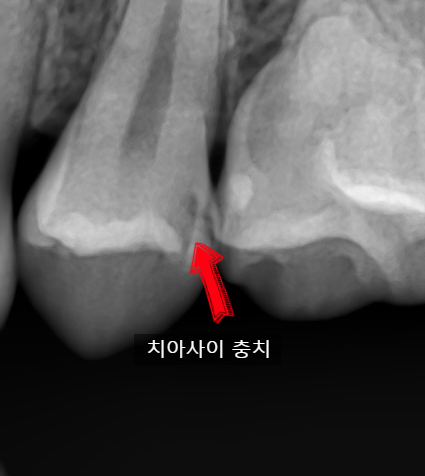

아래 사진은 또 다른 치아 사이 충치가 있는 치아의 엑스레이 사진입니다.

치아 겉에서는 까맣게 보이지 않지만 엑스레이에서는 보이는 치아사이 충치